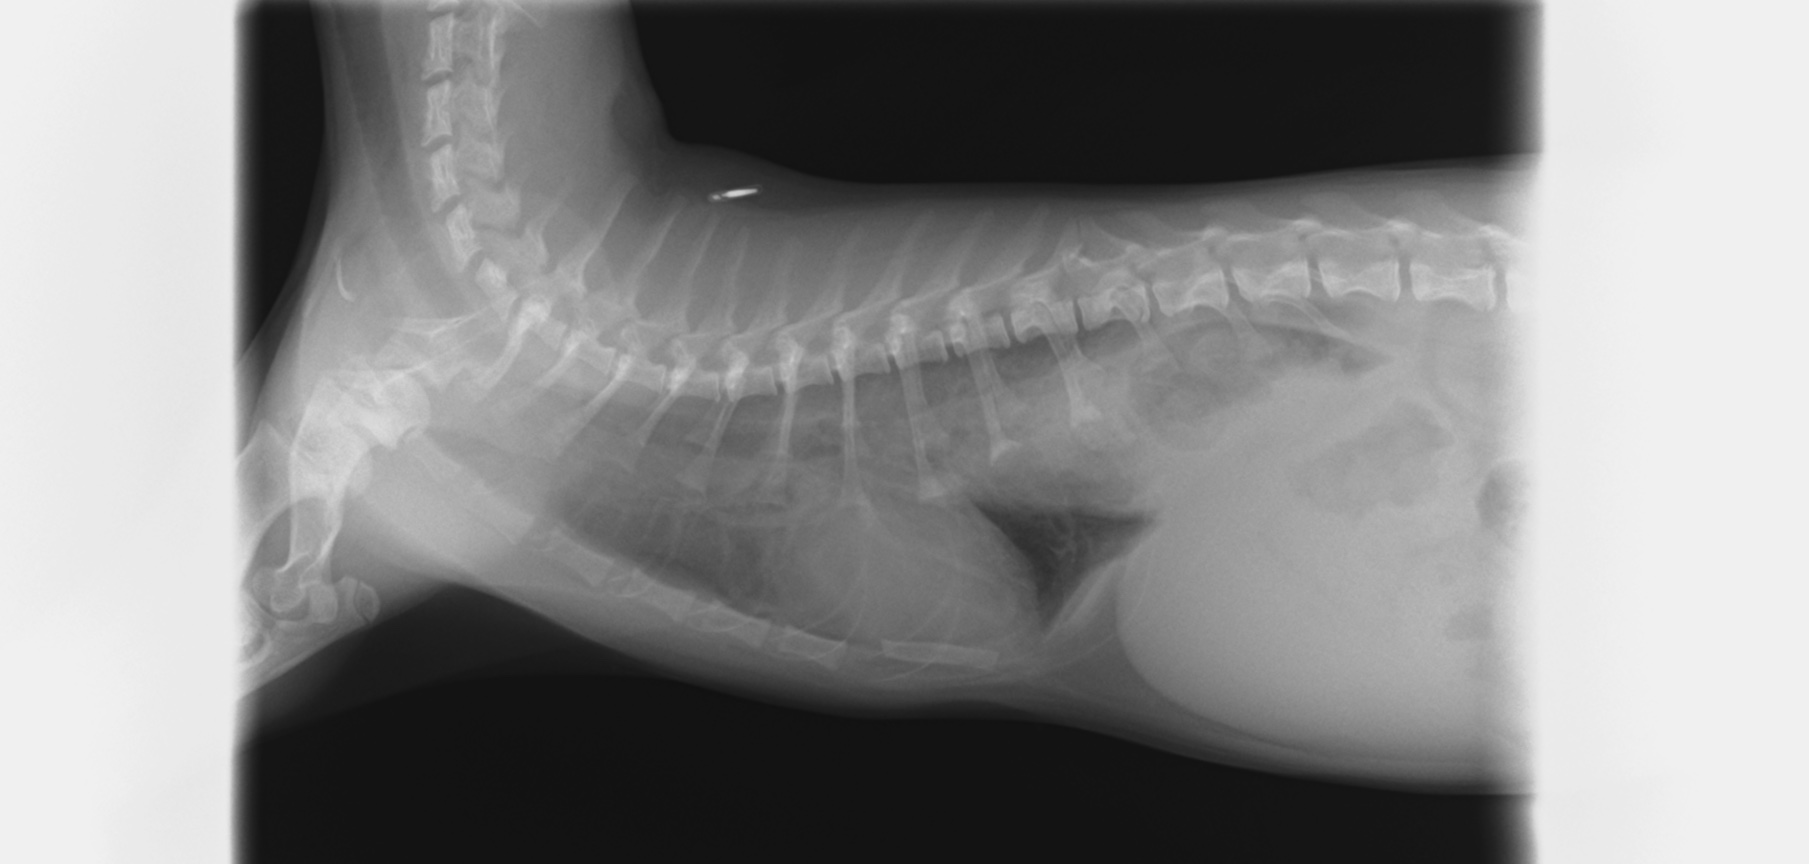

食道裂孔ヘルニア

2024/11/06